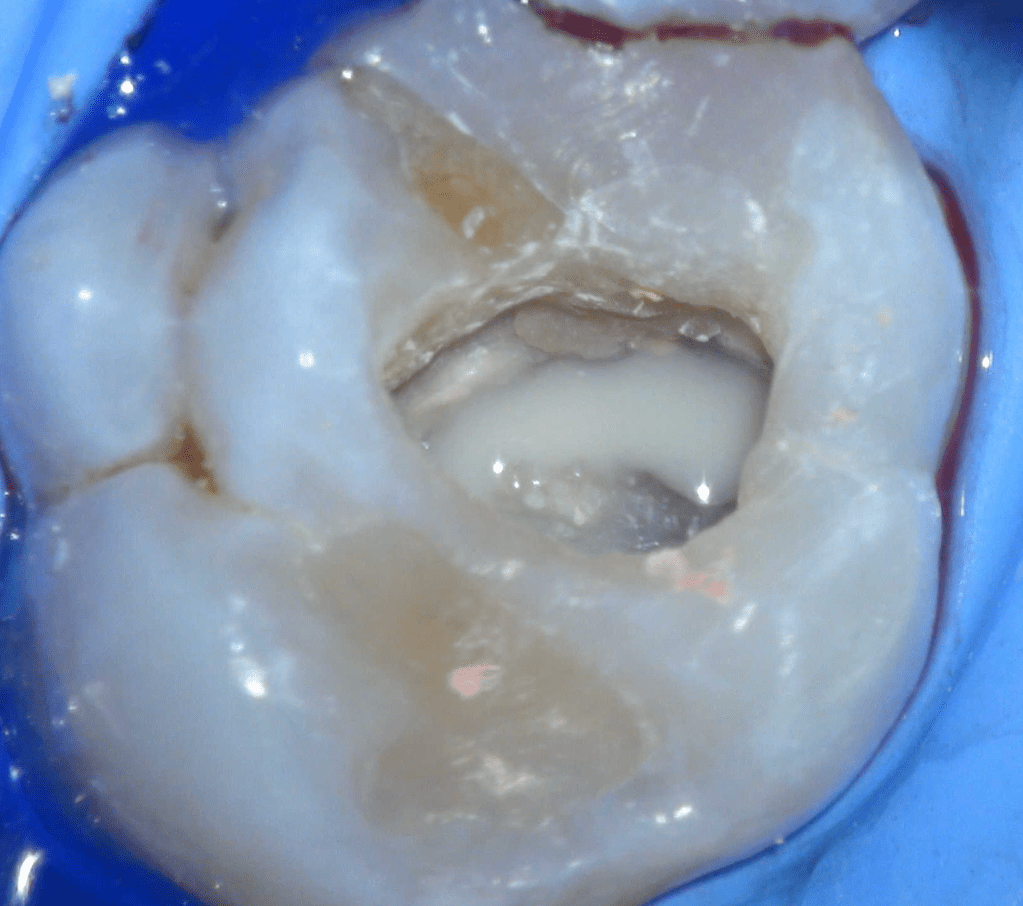

Reco preendo + 4 conductos molar superior